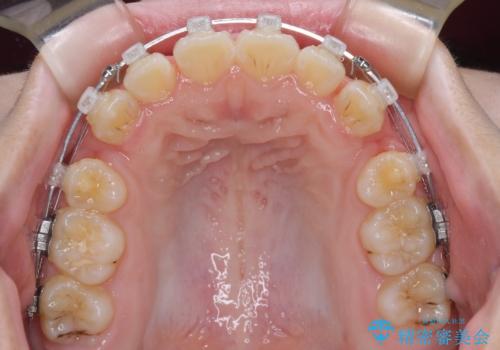

- クリアブラケット

上下左右の第一小臼歯4本を抜歯し、ワイヤー装置での抜歯矯正を行っていくのですが、原因である舌の突出癖を改善しないことには治療がうまく進められないため、舌のトレーニングを徹底するよう指導していくこととしました。

当初は舌のトレーニングがうまくできていなかったのですが、途中から奏効し、非常に短い期間で治療を終えることができました。